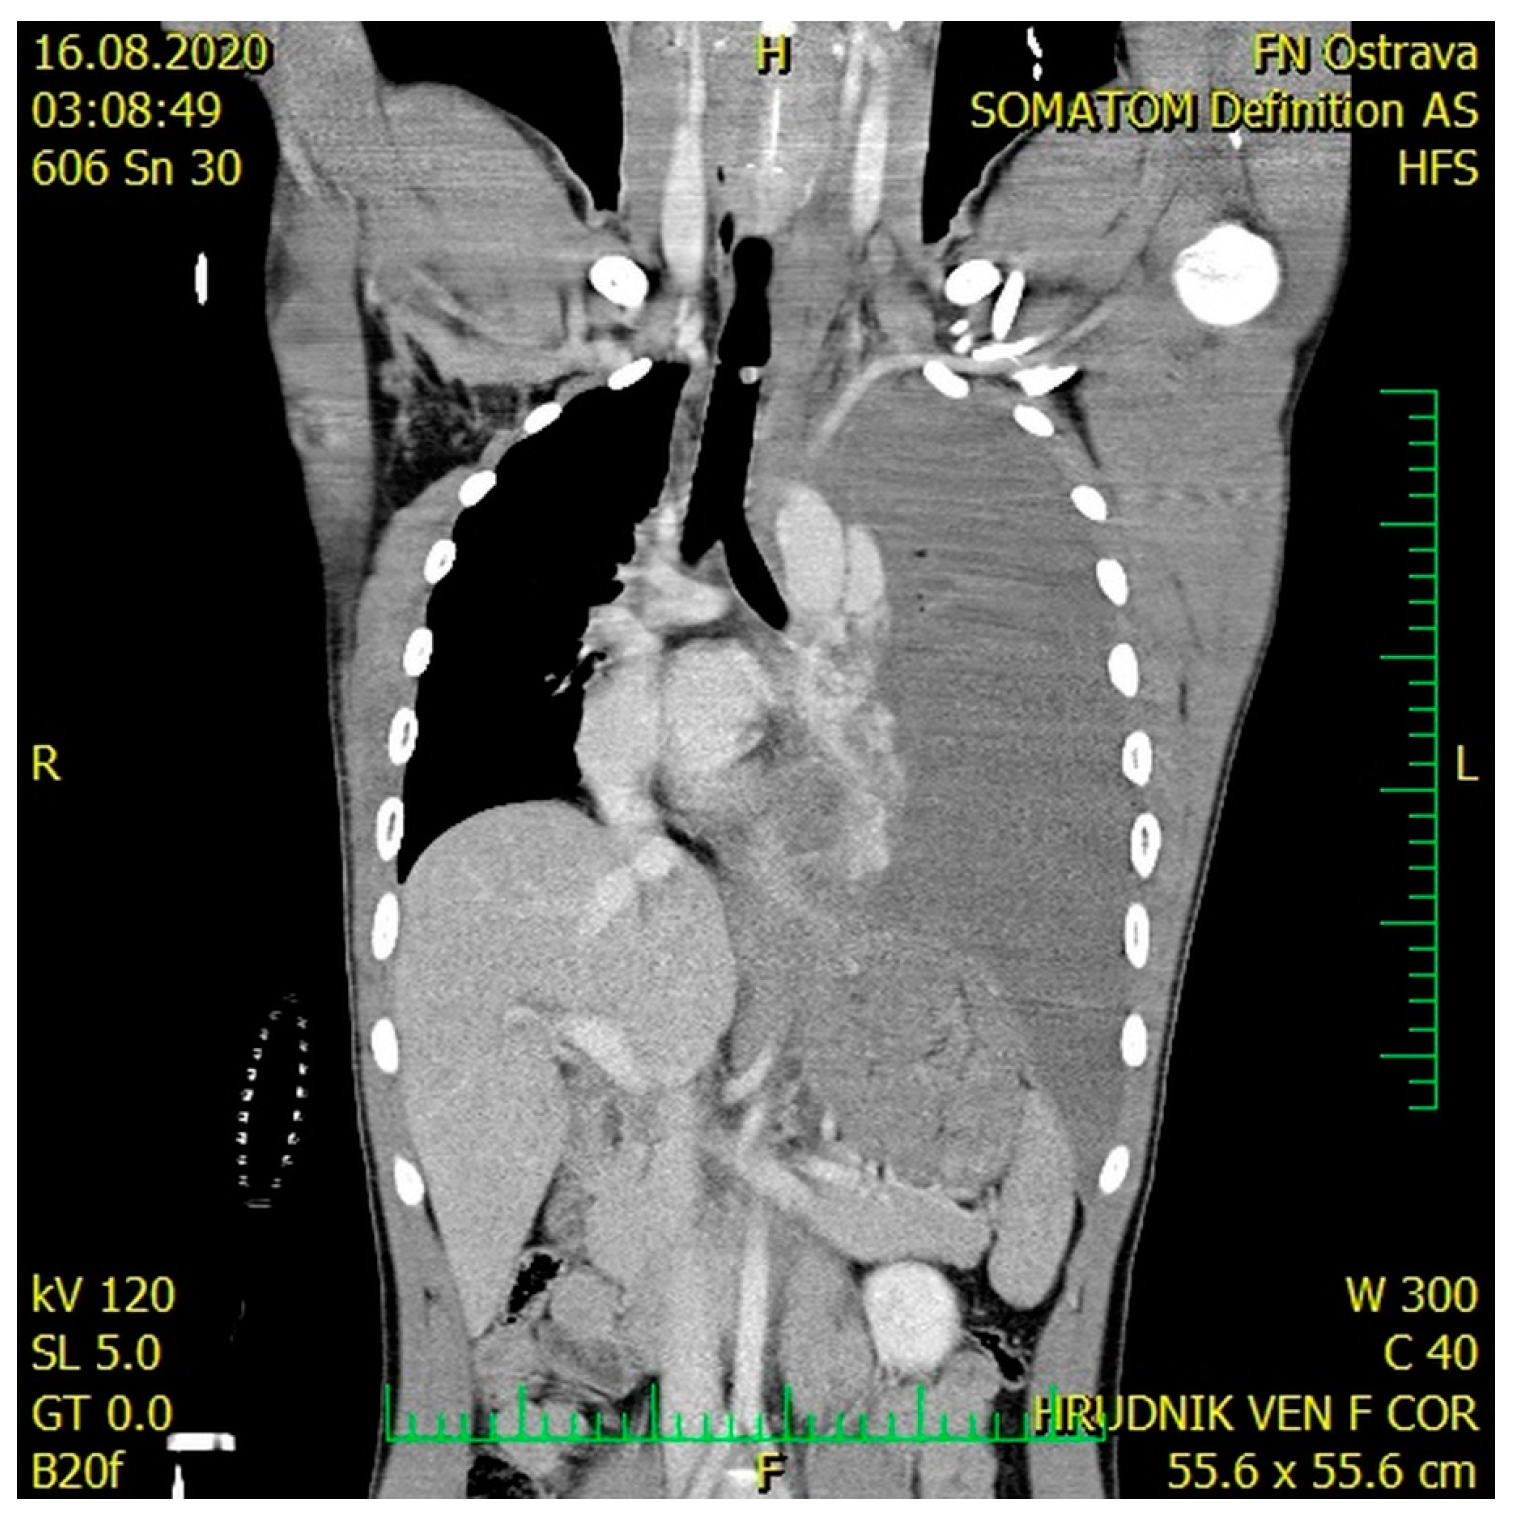

Tension Hemothorax in Aortic Rupture: A Case Report

2. Case Presentation